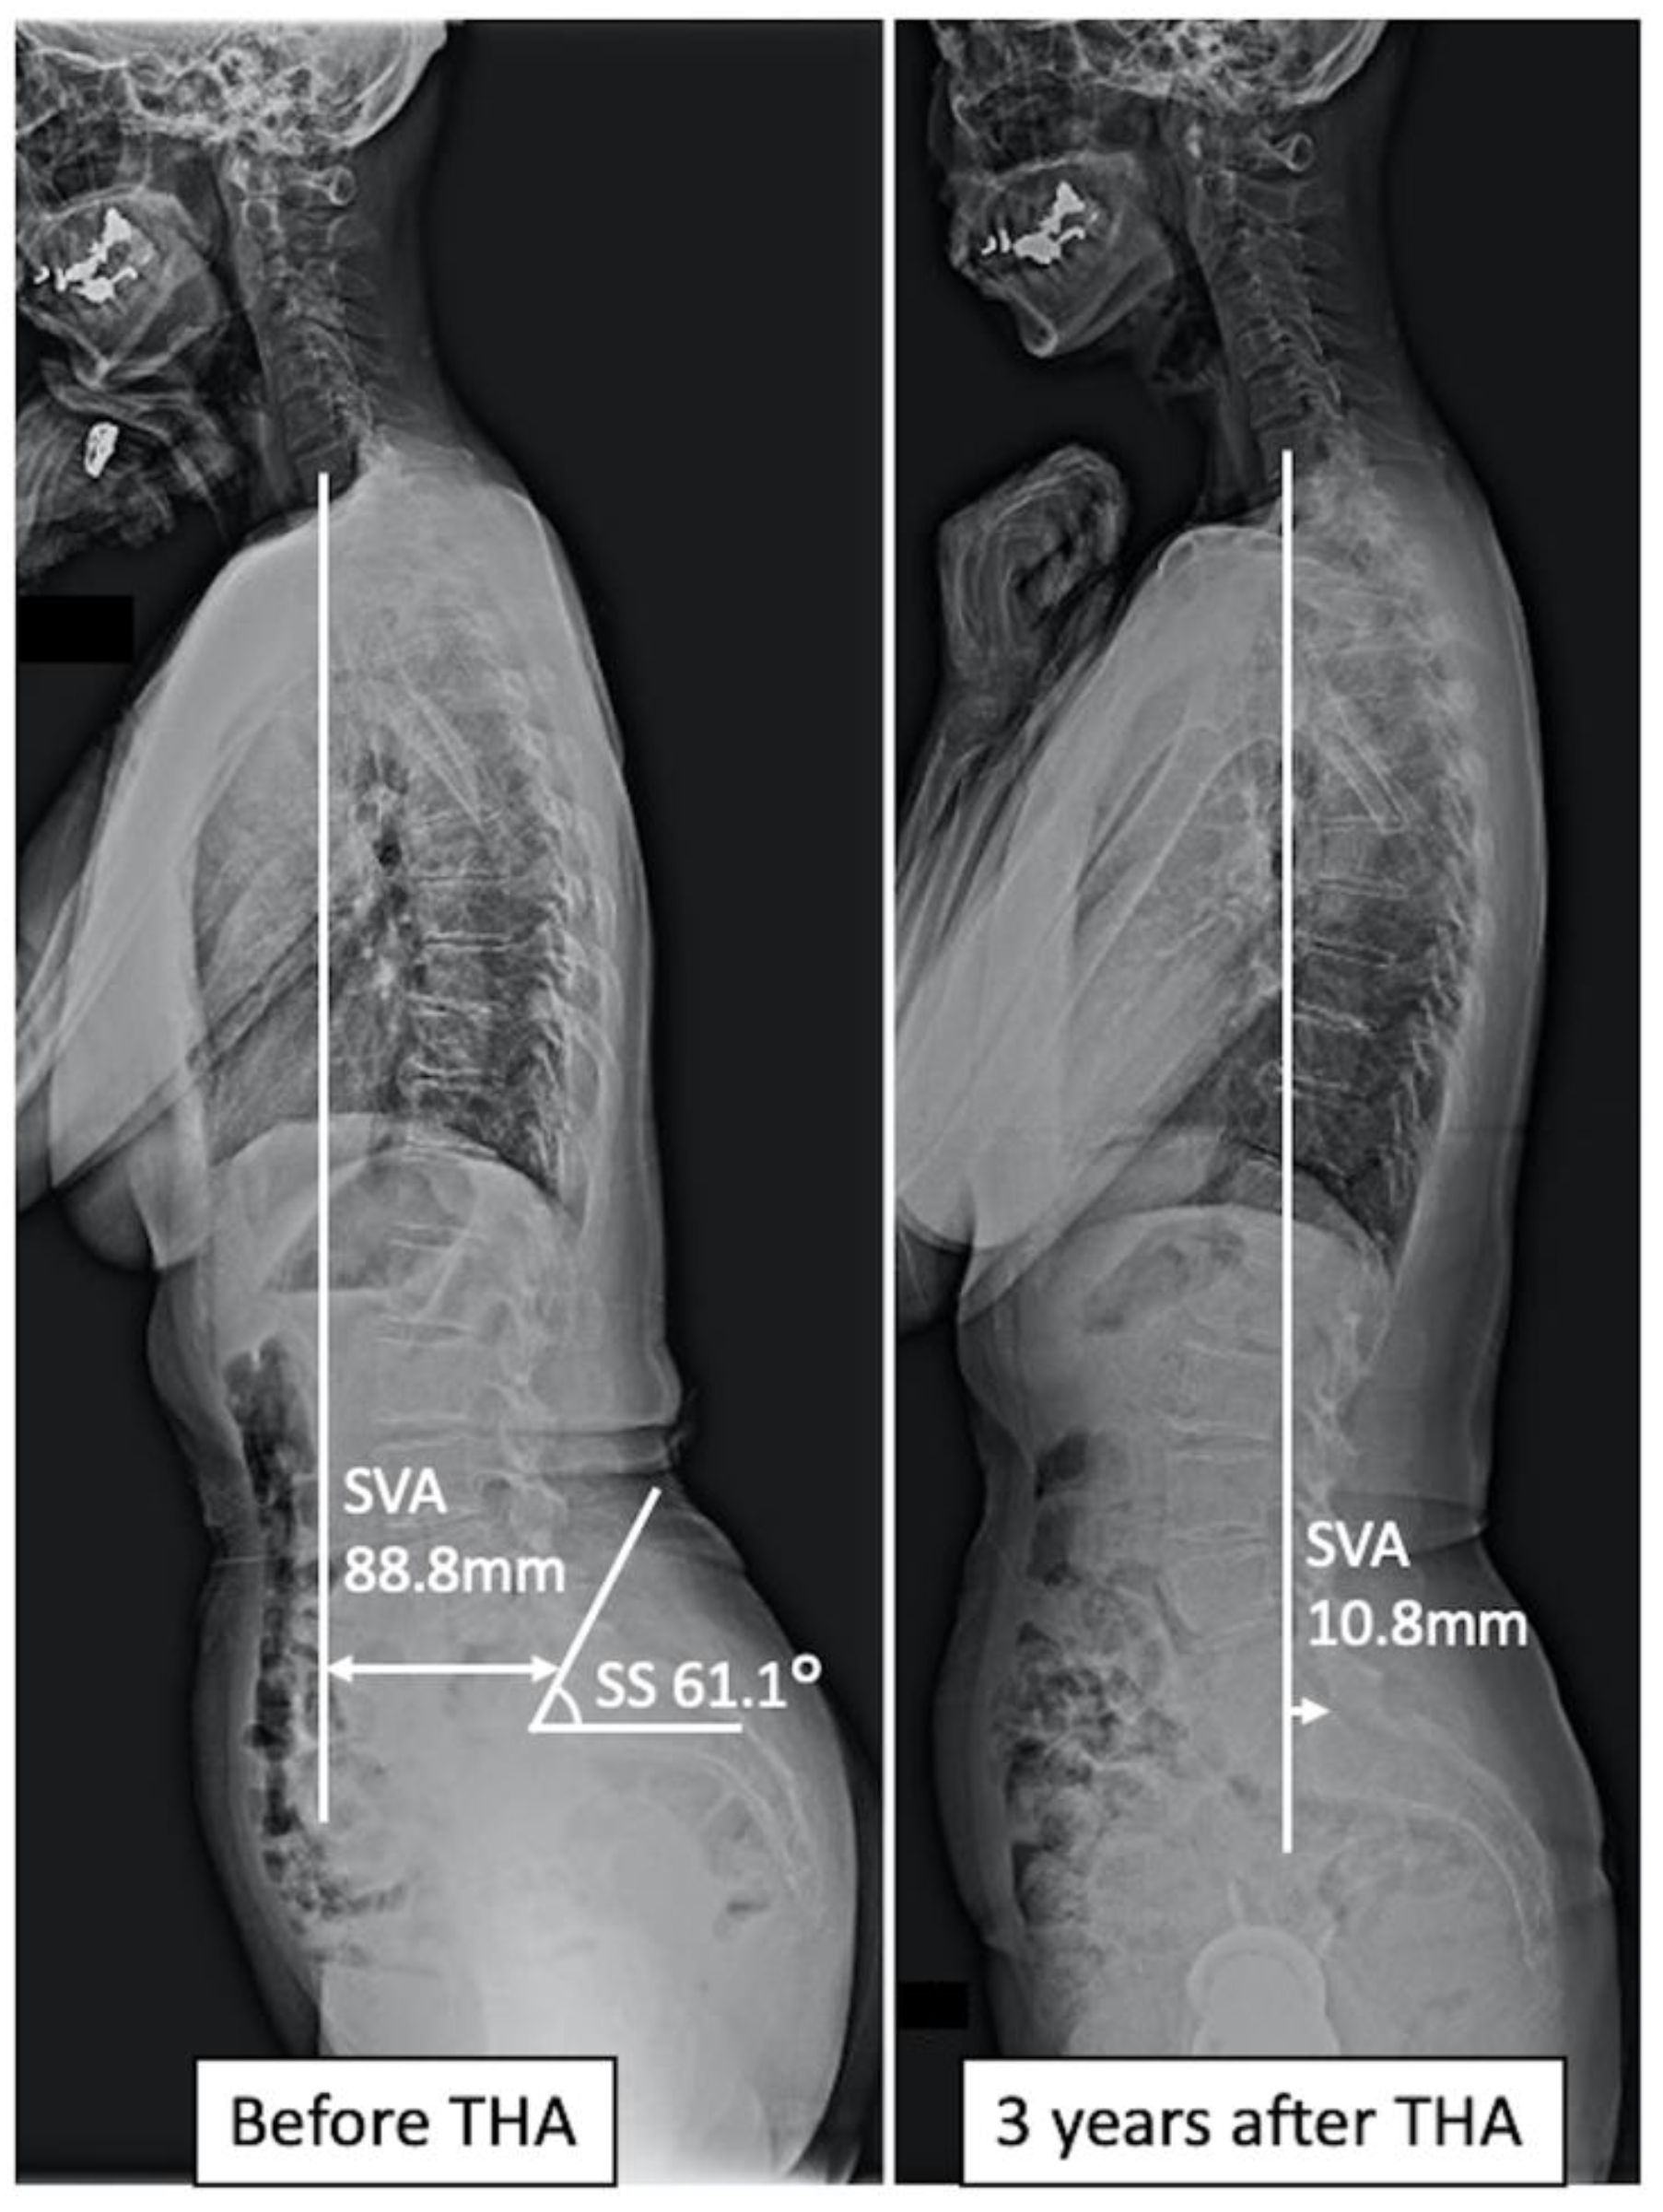

| SVA (mm), mean ± SD | 47.9 ± 26.1 | 45.3 ± 47.2 | 0.665 |

| SS (degrees), mean ± SD | 32.7 ± 10.2 | 42.7 ± 12.4 | 0.006 |